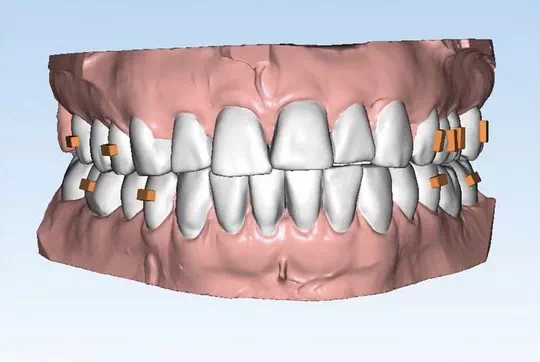

Invisalign Orthodontic treatment - What to expect?

Invisalign emerges as an innovative teeth-straightening system, utilizing successive see-through aligners that are custom- manufactured to re-align your teeth over time. This revolutionary method treats mild-to-moderate malocclusions such as spacing, crowding, protruding incisors, overbite, underbite, crossbite and open bite which are reported to improve bite alignment and overall oral function.